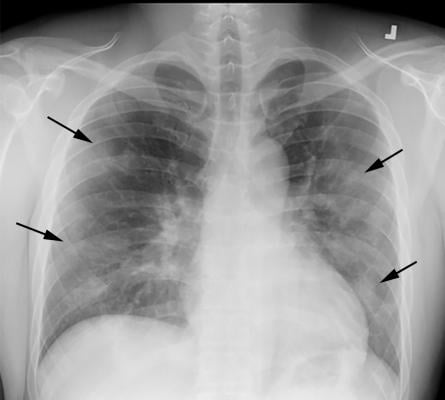

COVID-19 progression over 4 days in a 28-year-old man. This posteroranterior chest X-ray \ shows bilateral multiple peripheral and lower lobe ground glass opacities (GGOs) shown by the arrows. Image courtesy of Margarita Revzin et al.

In a new paper published May 31 in Nature Machine Intelligence, UW researchers examined multiple models recently put forward as potential tools for accurately detecting COVID-19 from chest radiography, otherwise known as chest X-rays. The team found that, rather than learning genuine medical pathology, these models rely instead on shortcut learning to draw spurious associations between medically irrelevant factors and disease status. Here, the models ignored clinically significant indicators and relied instead on characteristics such as text markers or patient positioning that were specific to each dataset to predict whether someone had COVID-19.